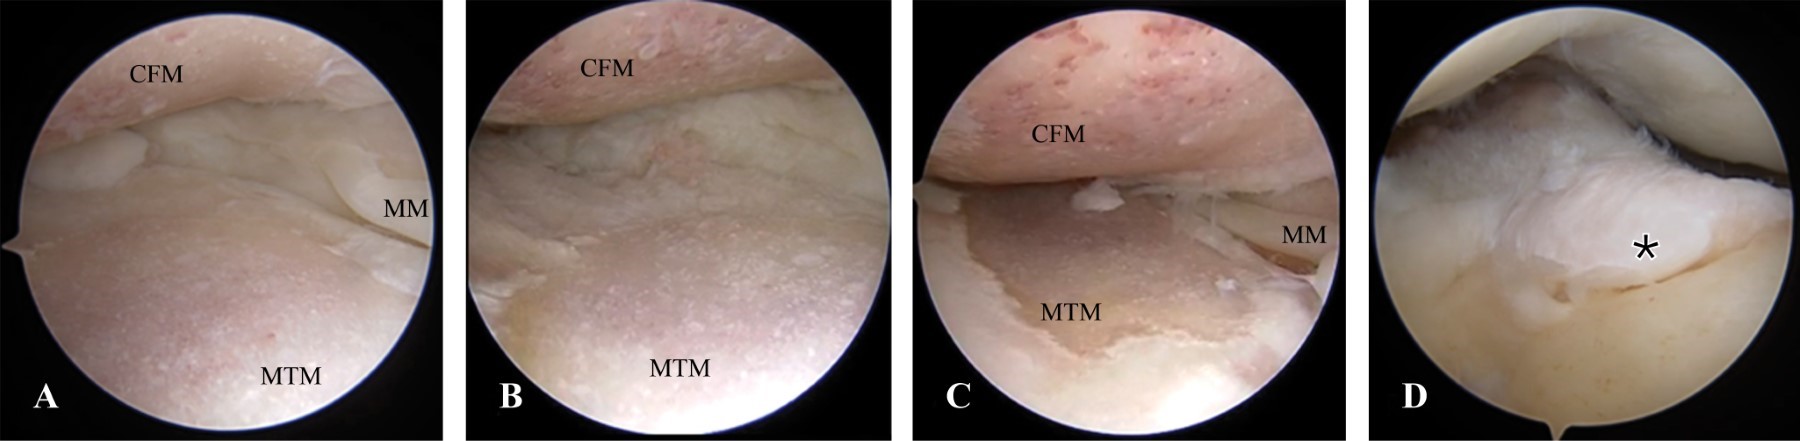

Se procede a realizar artroscopía, se evidencia: escotadura cerrada, ruptura completa inveterada de LCA, pinzamiento de LCP, ruptura del cuerno posterior y cuerpo de menisco lateral, ruptura crónica inveterada y extruida de menisco medial, pinzamiento femorotibial anterior, cuerpos libres intraarticulares, lesión condral de 1 cm2 en cóndilo femoral lateral en zona de carga, artrosis grado IV de compartimento medial de rodilla, sinovitis subcuadricipital (Figuras 4, 5, 6 y 7).

Durante la artroscopía, se realiza escotaduroplastía, liberación de LCP, desbridamiento de osteofito en espina tibial anterior, meniscectomía parcial de flap inferior del cuerno posterior y cuerpo de menisco lateral, meniscectomía parcial de raíz meniscal posterior remanente de menisco medial, extracción de cuerpos libres osteocondrales posteromediales, mediales y subcuadricipitales, remodelación de lesión condral en cóndilo femoral lateral en zona de carga, desbridamiento condral en periferia de cóndilo femoral medial (periartrosis), sinovectomía subcuadricipital (Figuras 4, 6, 7 y 8).